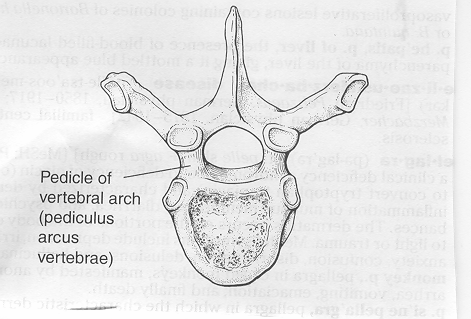

Figura

3. Assetto delle coste nella scoliosi strutturata (G. Bartolozzi,

Gugliemi M. Pediatria, Principi e pratica clinica, Elsevier

2008, pag. 1233)

vertebrali che nei pedicelli dell'arco vertebrale (Figura

3). Ricordo che l'ossificazione può essere encondrale

Figura

4. I pedicelli dell'arco vertebrale